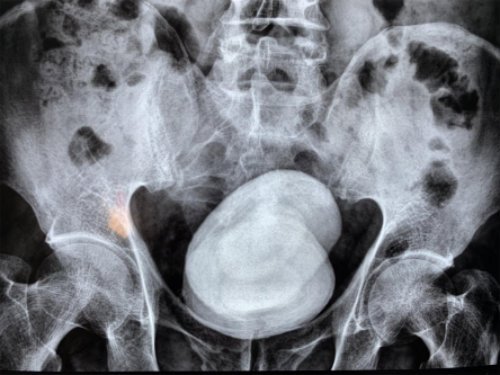

1、2019年10月8日,江西豐城的鄭先生在武漢京都結(jié)石醫(yī)院取出兩塊巨型膀胱結(jié)石,倆結(jié)石都有成年人拳頭大,如此巨大的結(jié)石在全國(guó)范圍內(nèi)也十分罕見,該案例被省內(nèi)多家知名媒體跟蹤采訪報(bào)道。

鄭先生無視膀胱結(jié)石20多年,結(jié)果小顆粒結(jié)石一晃長(zhǎng)成拳頭大小,差點(diǎn)把膀胱撐壞。近日,他實(shí)在“忍無可忍”,慕名求助于武漢京都結(jié)石醫(yī)院,醫(yī)生成功為他取出兩顆七八公分大的結(jié)石。見到結(jié)石實(shí)物后,鄭先生嚇出一身冷汗。

經(jīng)查,鄭先生的膀胱被兩顆直徑長(zhǎng)達(dá)七八公分的結(jié)石充滿,從X光片上看,這對(duì)超大號(hào)結(jié)石就像一對(duì)“雙胞胎”,霸占著他的膀胱。因結(jié)石巨大,醫(yī)生只能采用膀胱切開取石的方法將石頭取出。當(dāng)醫(yī)生把兩個(gè)拳頭大的結(jié)石拿給他看時(shí),他對(duì)自己久拖不治的行為懊悔不已。